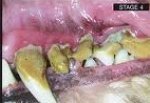

Chronic bacterial infection is present; it is destroying the gum, tooth, and bone. At this stage, bacteria may be spreading throughout the body via the bloodstream, which can cause damage to the liver, kidneys, and heart.